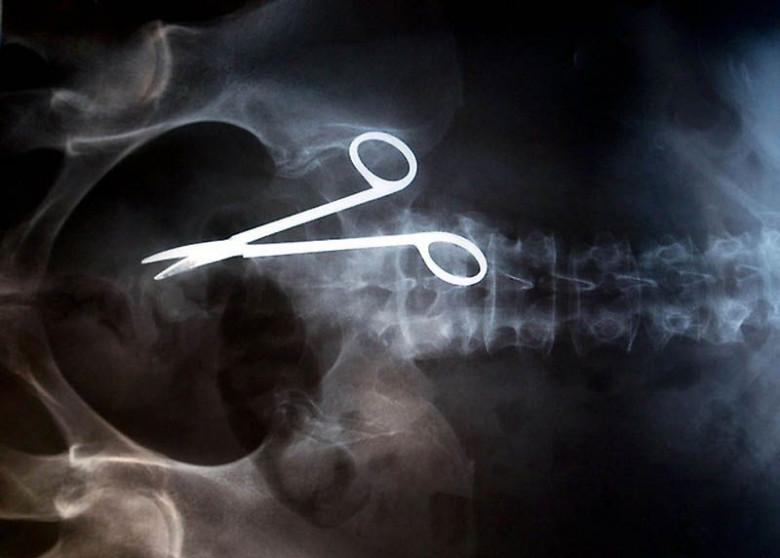

12. Վիրահատական մկրատ, որը մոռացել են հիվանդի մարմնում վիրահատությունից հետո